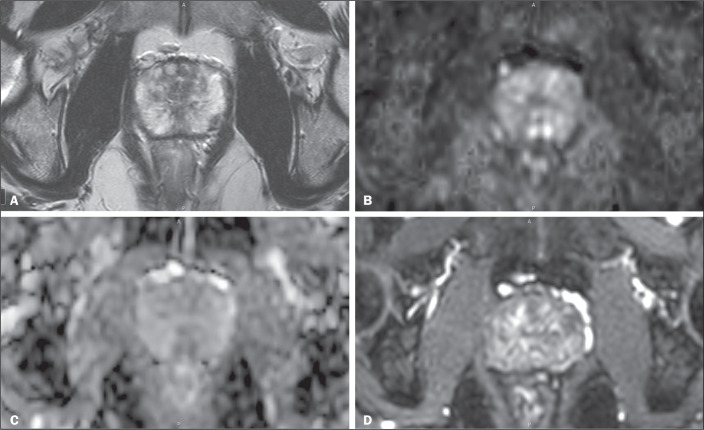

Objective: To determine the proportion of men with completely negative multiparametric magnetic resonance imaging (MRI) scans and which individual sequence-T2-weighted imaging (T2WI) or diffusion-weighted imaging (DWI)-best predicts an overall negative examination result.

Materials and methods: This was a single-center retrospective study evaluating 492 MRI scans compliant with Prostate Imaging Reporting and Data System (PI-RADS), version 2.1. Radiology reports described the absence of lesions or suspicious lesions with PI-RADS scores of 3-5, signifying positive T2WI or DWI results. Positivity on a dynamic contrast-enhanced (DCE) study was determined by early or simultaneous focal enhancement consistent with lesions on T2WI or DWI. All scans reported as negative were prospectively reviewed to ensure that each sequence truly met the criteria for negativity according to the PI-RADS guidelines. Descriptive statistics were employed to summarize the data, and the chi-square test was employed to assess the relationship between a negative T2WI result and a negative DWI/DCE result, as well as that between a negative DWI result and a negative DWI/DCE result, with logistic regression models identifying predictors of such combined results.

Results: Among the patients evaluated, approximately one-third of those with suspected prostate cancer and 10% of those with known cancer could have concluded their examination after a single negative sequence. A negative T2WI result predicted negative DWI/DCE findings in 62.4% of scans (95% CI: 55.3-68.9), with an odds ratio of 245.3 (p < 0.001). Similarly, a negative DWI result predicted negative T2WI/DCE findings in 88.9% of scans (95% CI: 83.1-92.7) with an odds ratio of 76.4 (p < 0.001). These associations remained robust after adjustment for age, prostate-specific antigen level, prostate-specific antigen density, cancer status, and radiologist.

Conclusion: Findings from T2WI or DWI may serve as preliminary indicators for the subsequent diagnostic yield of other sequences, with DWI appearing to hold a slight advantage. Although the accuracy of this approach is not yet sufficient for clinical implementation, these results are promising and merit further investigation.